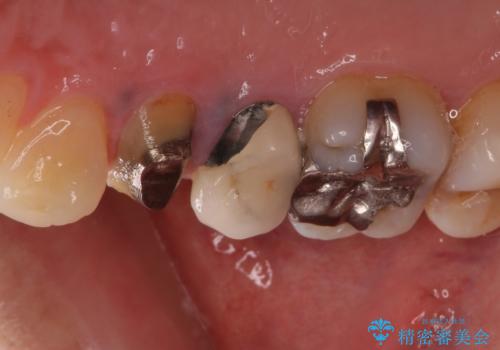

- クラウンが割れて治療を行っていたものの、途中で放置してしまったとのことで来院された患者様です。

根管治療を行った後に、ガラス系セラミッククラウンにて補綴することとしました。